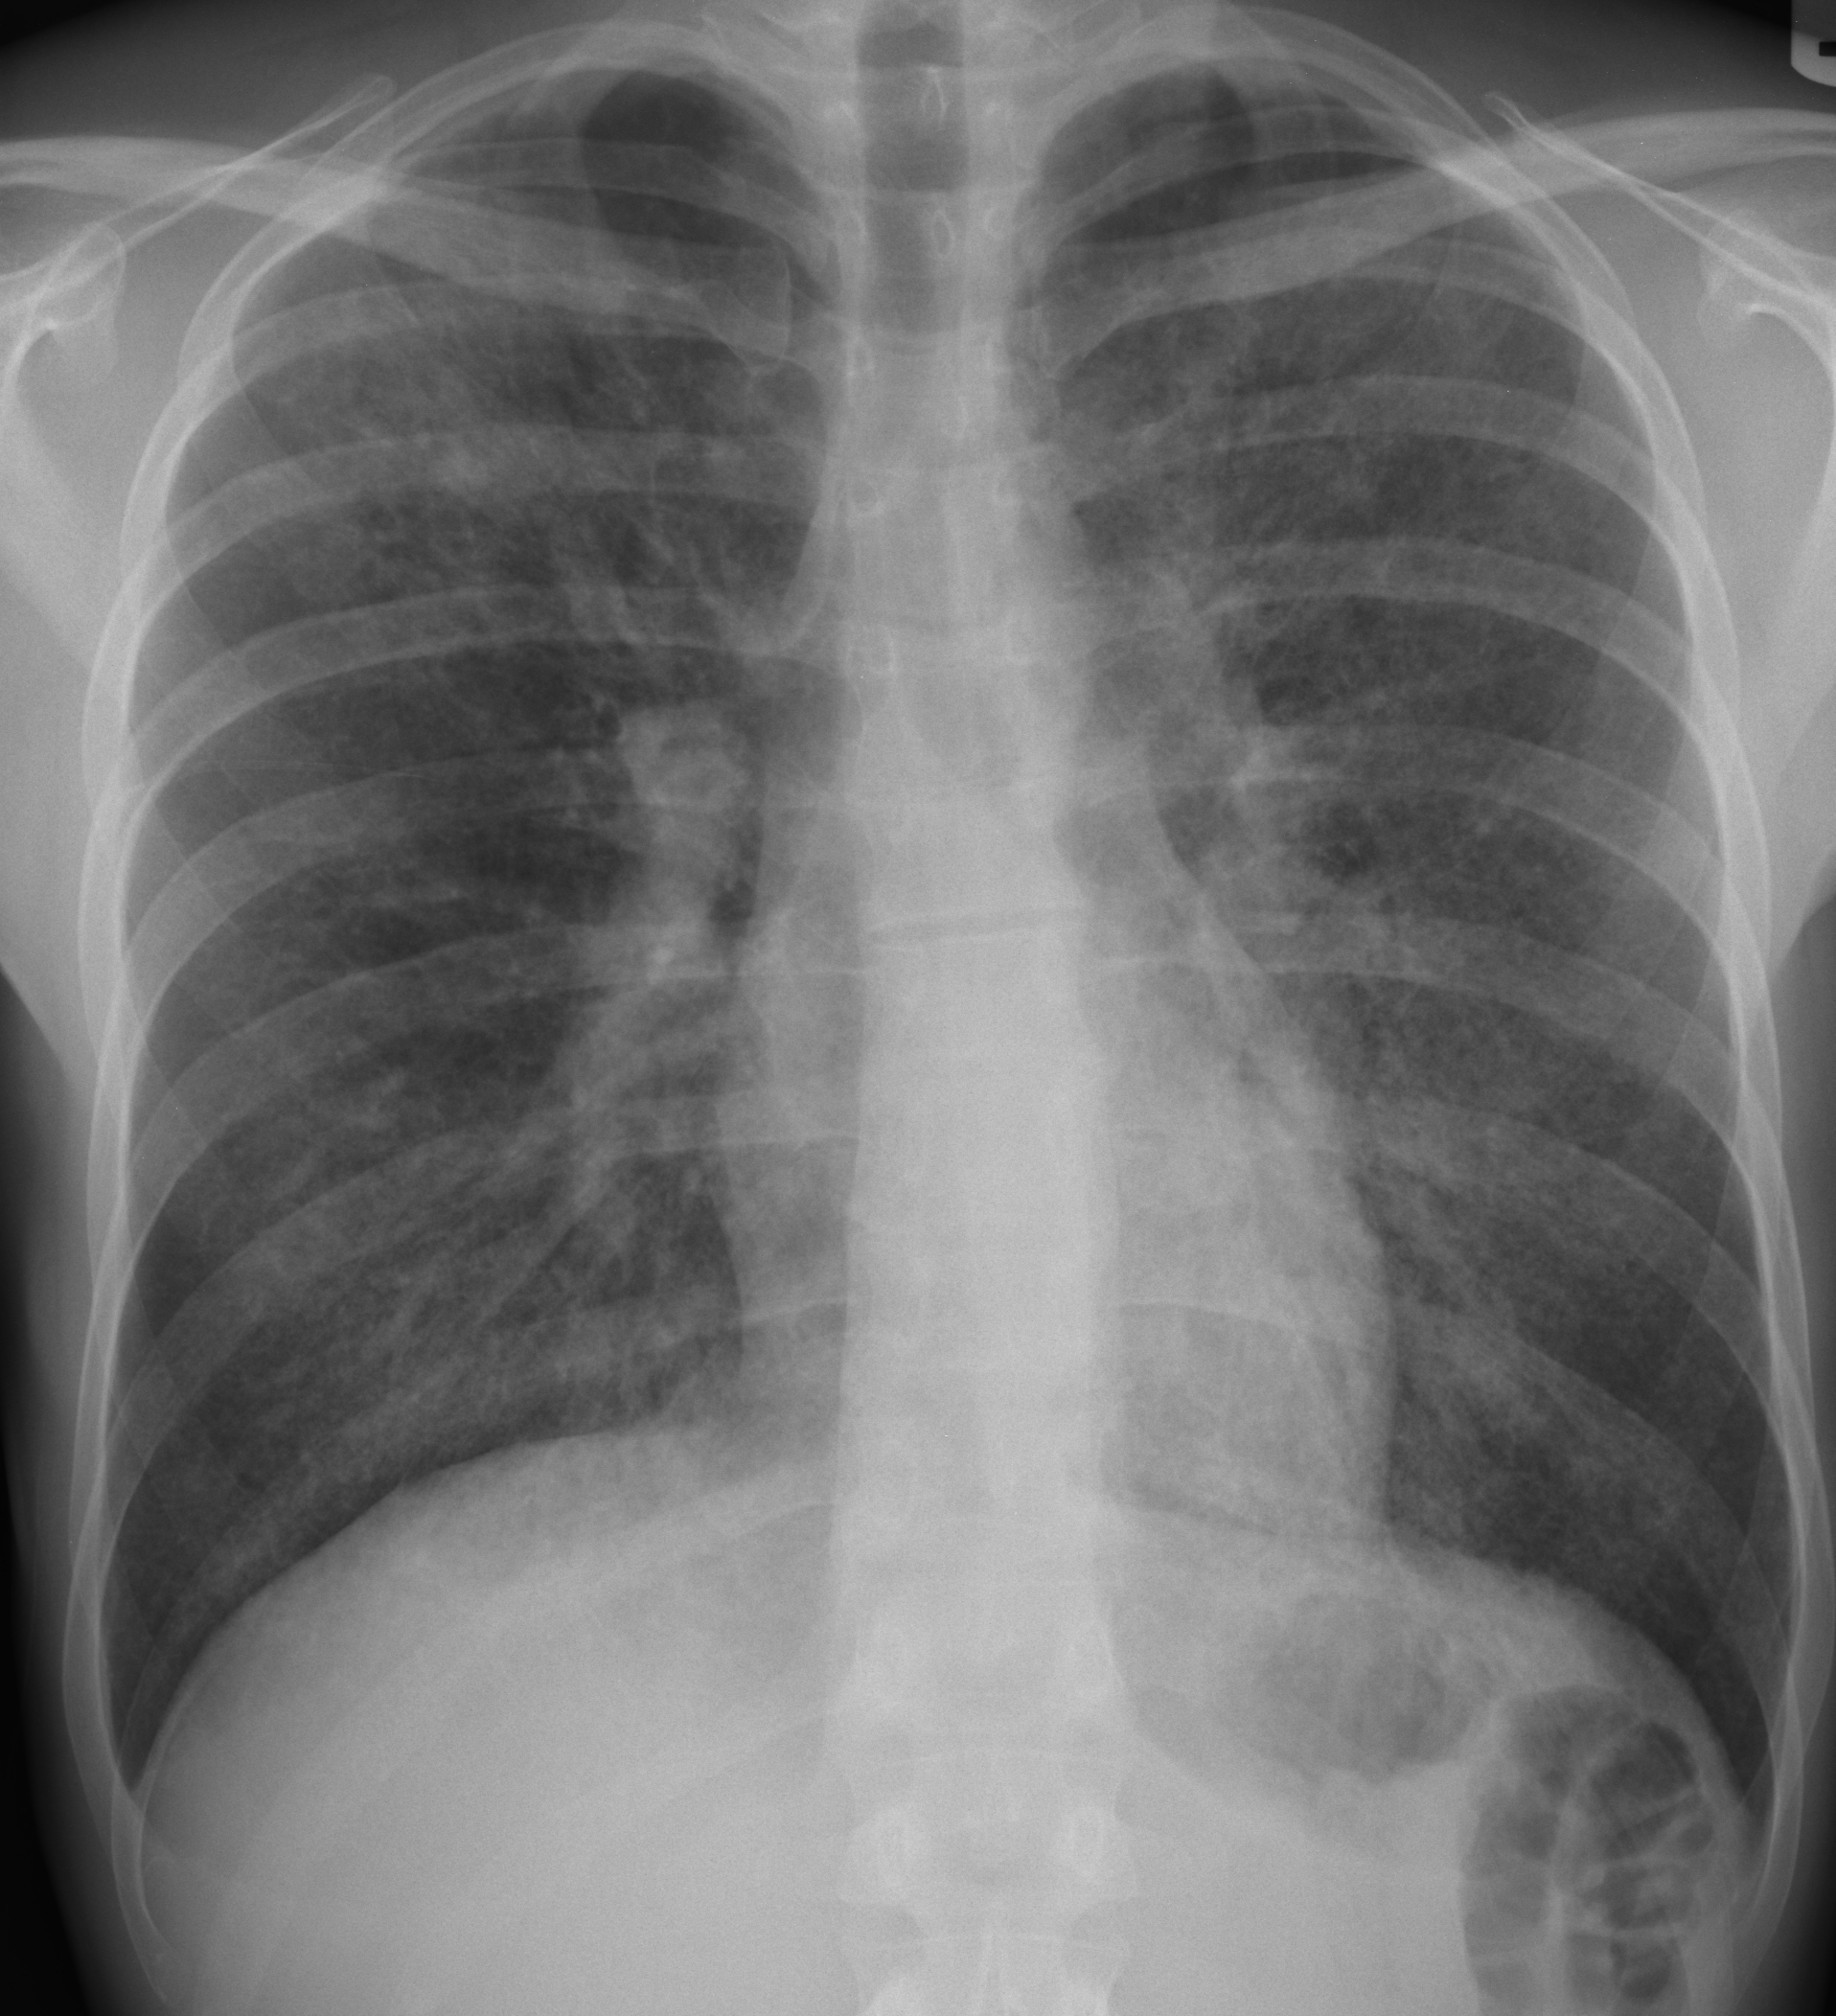

Chest X-ray

Patient presents with fever, fatigue, and shortness of breath. Chest auscultation reveals mild crackles in lower lobes. No signs of cyanosis. Patient is alert and oriented.